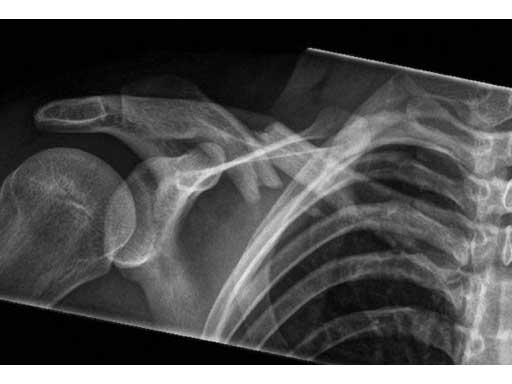

A 21-year old male fell on the right shoulder when playing soccer. He sustained a cavicular shaft fracture type 06 A3 (OTA classification) with dislocation of shaft width and shortening of around 2 cm.

Fig 1ab Preoperative x-rays.